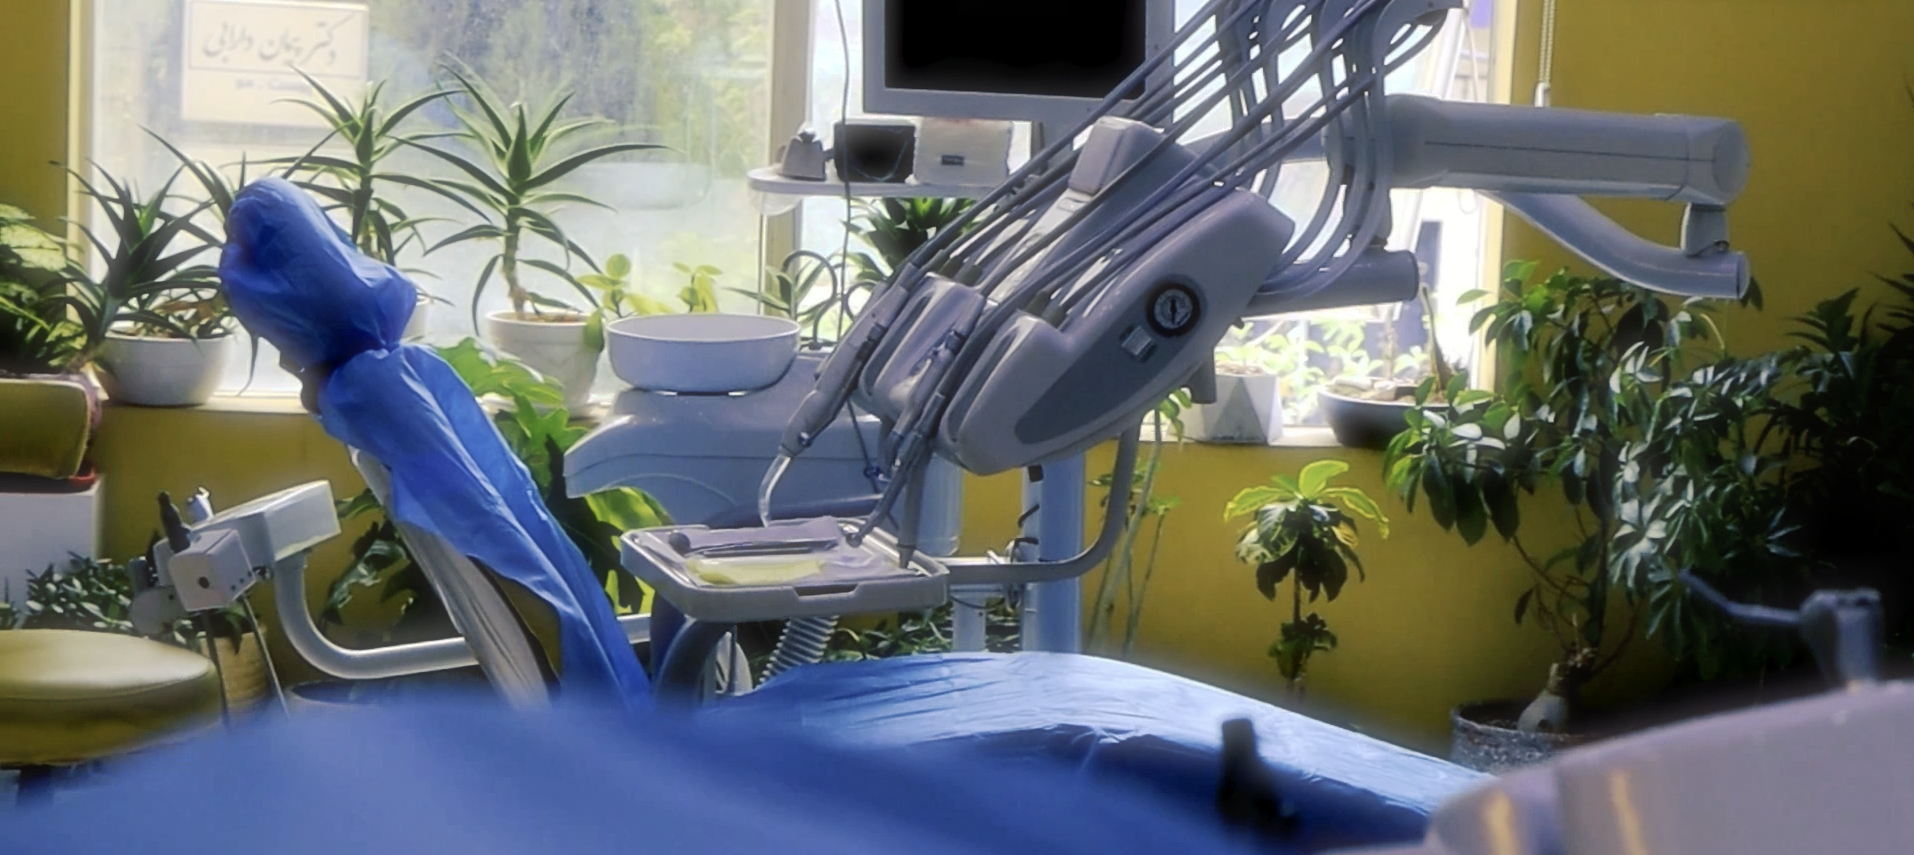

به کلینیک دندانپزشکی دکتر علی نورافروز خوش آمدید

کلینیک دندانپزشکی دکتر علی نورافروز با محیطی آرام و کادری مجرب اماده خدمت رسانی و مشاوره به شما می باشد